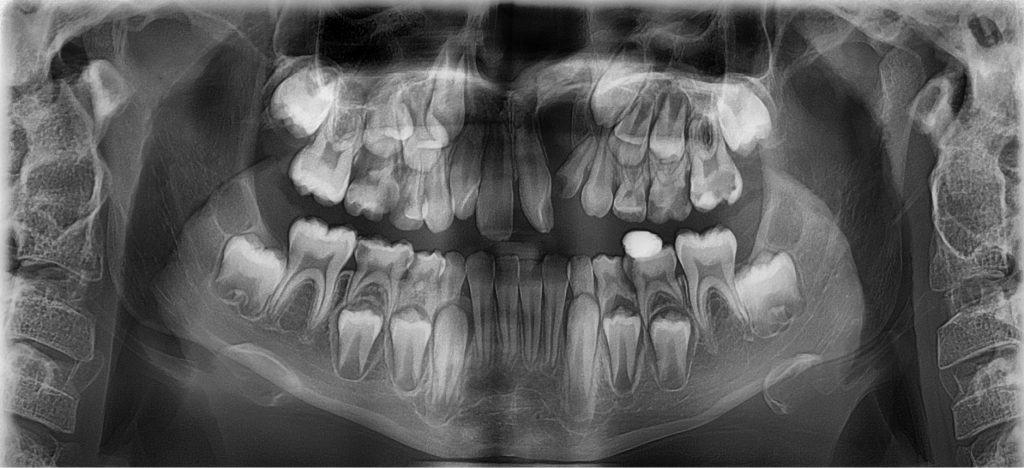

Streszczenie: Diastema jest przykładem szparowatości między zębami siecznymi przyśrodkowymi i może być spowodowana różnymi czynnikami. Występuje ona fizjologicznie, w przypadku wymiany uzębienia mlecznego na stałe bądź jest spowodowana zaburzeniami zarówno wrodzonymi, jak i nabytymi. Ich przykładem jest występowanie zęba nadliczbowego, hipodoncji jako przeszkody w wyrzynaniu, przedwczesnej utraty zębów siecznych bocznych. Wśród przyczyn pozazębowych wyróżnia się: przerośnięte wędzidełko wargi górnej, torbiel w przednim odcinku szczęki czy też rozszczep podniebienia. Uzupełnieniem badania klinicznego w diagnostyce diastemy jest diagnostyka obrazowa, tj.: zdjęcie RTG zębowe, pantomogram, CBCT. Badania te dostarczają szczegółowych informacji na temat etiologii zaburzenia oraz umożliwiają dobór odpowiedniego postępowania terapeutycznego.

Diastema jest nieprawidłowością zębową, która dotyczy od 1,6% do 24,5% osób dorosłych [1]. Dla wielu pacjentów stanowi ona znaczący problem estetyczny, który często powikłany jest zaburzeniami funkcjonalnymi. Prawidłowe postępowanie diagnostyczne składa się z badania klinicznego poszerzonego o diagnostykę radiologiczną. Diastema występuje fizjologicznie w tzw. okresie „brzydkiego kaczątka”, tj. przed wyrznięciem się kłów górnych, które według Proffita wyrzynają się około 11,5 roku życia [2, [...]